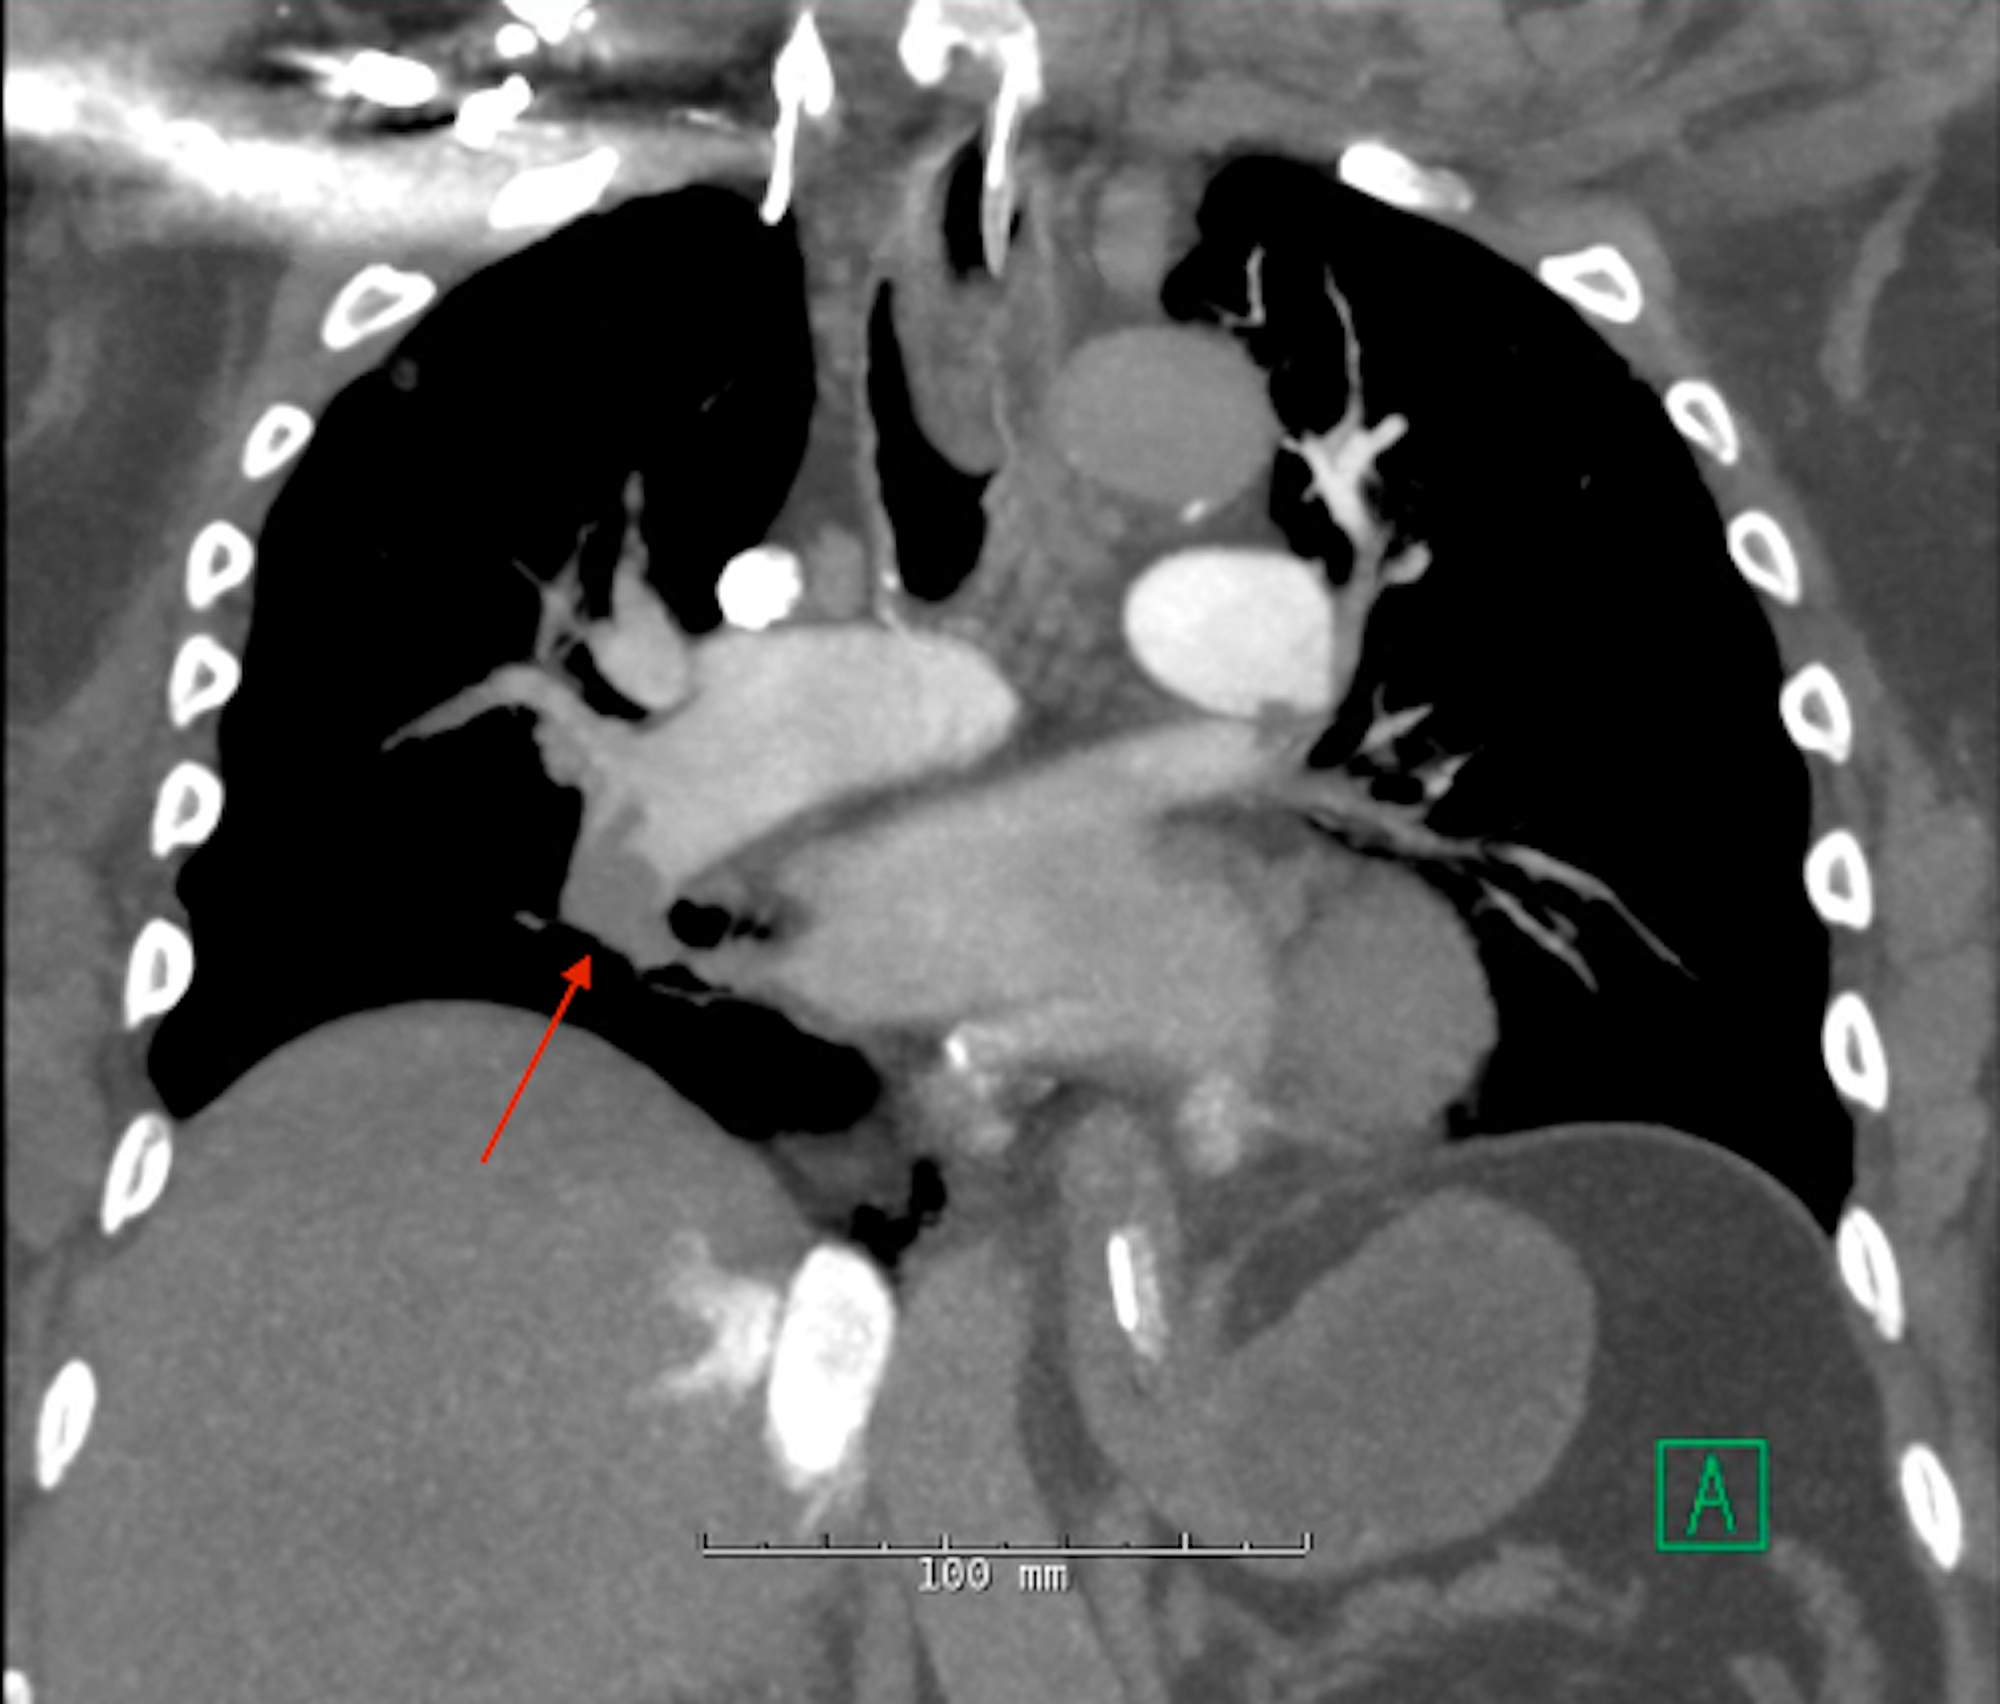

Figure 2 from Successful catheterdirected thrombolysis of a massive Pulmonary Embolism Catheter Directed Thrombolysis    thrombolytic therapy is used in patients with acute pulmonary embolism (pe) to rapidly dissolve the embolic burden and. Pulmonary Embolism Catheter Directed Thrombolysis.